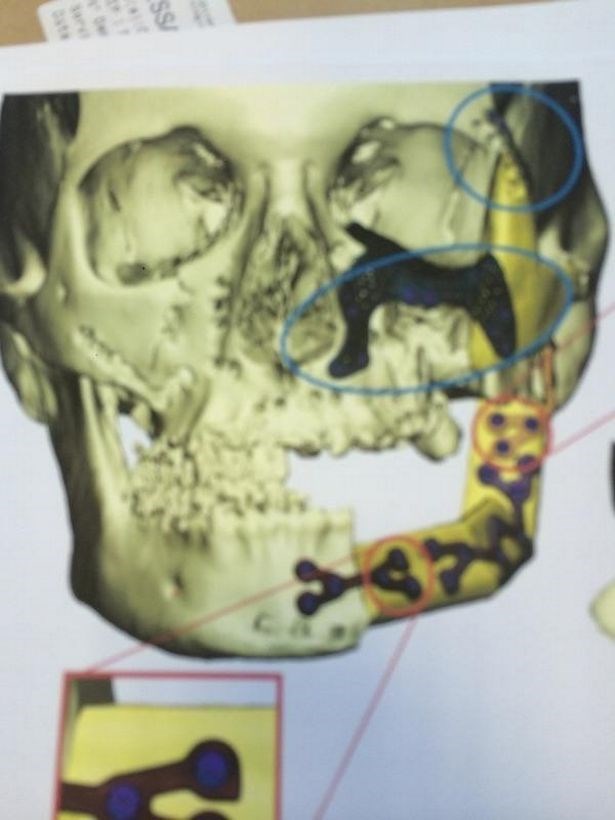

Από τον Νοέμβριο του 2015 έως σήμερα η 37χρονη μητέρα ενός επτάχρονου παιδιού έχει υποβληθεί σε 25 επεμβάσεις προκειμένου να γίνει ανάπλαση του προσώπου της. Χρειάστηκε να πάρουν οστό και να αναδομήσουν το θρυμματισμένο από τις σφαίρες πηγούνι της.